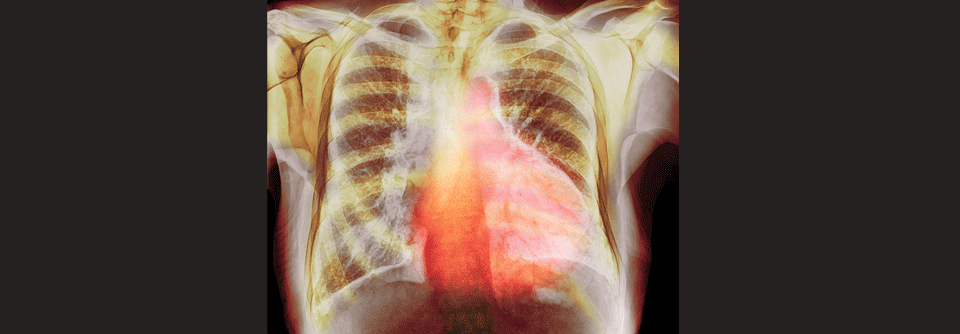

Unter optimaler Therapie regeneriert sich in den meisten Fällen die Herzfunktion vollständig, was häufig die Frage nach der Möglichkeit einer weiteren Schwangerschaft aufwirft. Unter optimaler Therapie regeneriert sich in den meisten Fällen die Herzfunktion vollständig, was häufig die Frage nach der Möglichkeit einer weiteren Schwangerschaft aufwirft. © Kostia – stock.adobe.com

Klagen Frauen gegen Ende der Schwangerschaft oder kurz danach über Dyspnoe, periphere Ödeme, Abgeschlagenheit und Herzrasen, kann eine peripartale Kardiomyopathie dahinterstecken. Frühzeitig erkannt und therapiert, ist die Prognose gut.

Die kardiologische Diagnostik der PPCM fußt neben der klinischen Untersuchung (Herzinsuffizienzzeichen) auf der Echokardiografie (reduzierte linksventrikuläre Auswurffraktion, meist in Verbindung mit dilatiertem linkem Ventrikel) und der Bestimmung des NT-proBNP (meist deutlich erhöht). Letztlich ist die PPCM allerdings eine Ausschlussdiagnose, betont Dr. Pfeffer.